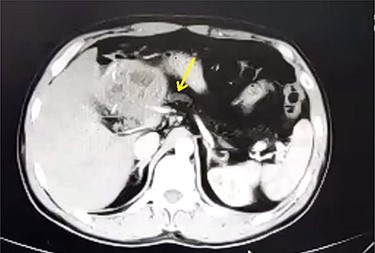

A 33-year-old male was referred to our Department of General Surgery, with a 3-month severe epigastric pain radiating to the back, associated with several episodes of green vomiting. Pain is episodic, relieved by painkillers, has no relation to food or movement. No history of changes in bowel habits or urine color. The patient reported a history of early satiety and an observed unmeasured weight loss. The past medical and surgical histories were irrelevant. Abdominal examination showed tenderness in the epigastric region, with no other signs. Laboratory tests including complete blood cell count, renal and liver function tests were within normal levels. Immunologic methods (ELISA) and indirect hemagglutination (IHA) assays were negative. Serum Amylase and CA 19-9 were within normal levels. Computed tomography (CT) scan revealed a multilocular cystic lesion in the head of the pancreas measuring 9.5 × 8.2 × 11 cm, causing external compression on the distal part of the CBD. The main pancreatic duct near the cystic mass is dilated measuring 0.5 cm. The gallbladder is distended (Figs 1 and 2).

Axial contrast-enhanced CT scan of the abdomen showing dilatation of the MPD (5 mm).